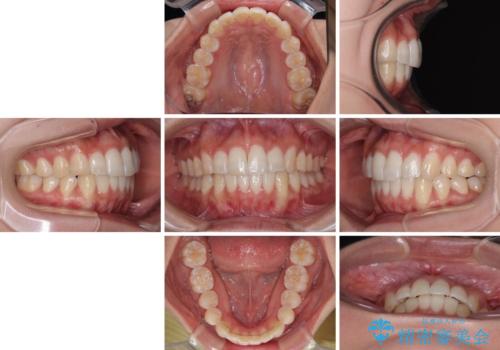

前歯のデコボコを治したい インビザライン矯正

- インビザライン・モデレート

- 1年5ヶ月

- 上下前歯の叢生を気にして来院された患者様です。

インビザラインでの治療を希望されていて、デコボコの程度が中等度であり、安価なパッケージにて対応可能と判断されたため、インビザライン・モデレートを用いて矯正治療を行うこととしました。